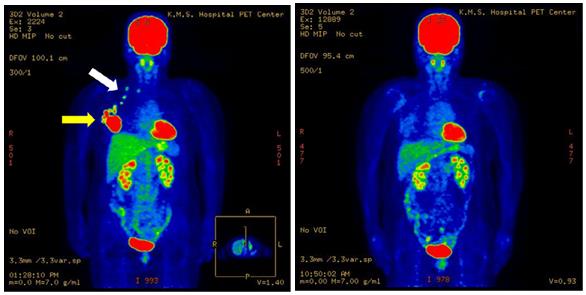

(图2)57岁女性,右乳癌进展期。左图为治疗前PET-CT图像。肿瘤病灶(黄色箭头),腋窝淋巴结转移,锁骨淋巴结转移(白色箭头)。右图为治疗后5年8个月的图像,未复发。